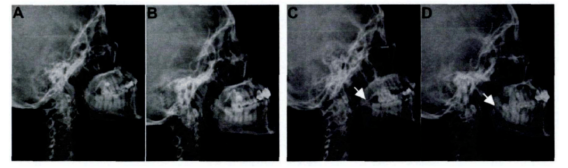

△臍帶間充質干細胞移植前后患者腮腺造影改變

11例口眼干燥的患者應用后2周時唾液流率顯著改善,1個月時升高2倍;除3例合并神經系統損害患者應用后效果不佳外,其余合并嚴重并發癥患者治療后均有不同程度的改善。接受MSC移植應用1個月后,患者血清中抗SSA與抗SSB抗體的滴度均顯著下降,其中抗SSB滴度下降幅度達50%,無不良反應發生。